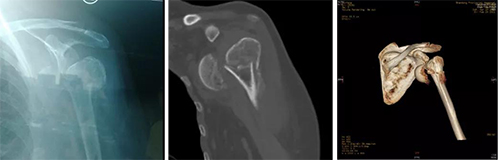

术前影像显示:肱骨近端粉碎骨折,肱骨头脱位、游离

患者来医院时已是伤后2个月,左肩疼痛并伴活动明显受限。主任医师李连欣接诊后认为,患者左肱骨近端骨折为四部分,骨折伴肩关节脱位,肱骨头翻转游离,加上早期治疗没有复位,成为陈旧性,治疗难度很大。经全科人员进行病例讨论分析后,大家认为这名患者的手术难点在于:患者59岁,如果骨折不是陈旧性,还是首选内固定,但是患者肱骨头翻转游离,已经失去血运,2个多月再予以复位,也难以恢复血运重建。该患者肱骨近端骨折为四部分骨折,粉碎并移位明显,不仅复位困难,内固定也难固定牢固,即使手术恢复其解剖关系,未来发生骨折移位肱骨头缺血坏死、创伤性关节炎等并发症的几率极高,最好行人工肩关节置换以恢复肩关节功能。